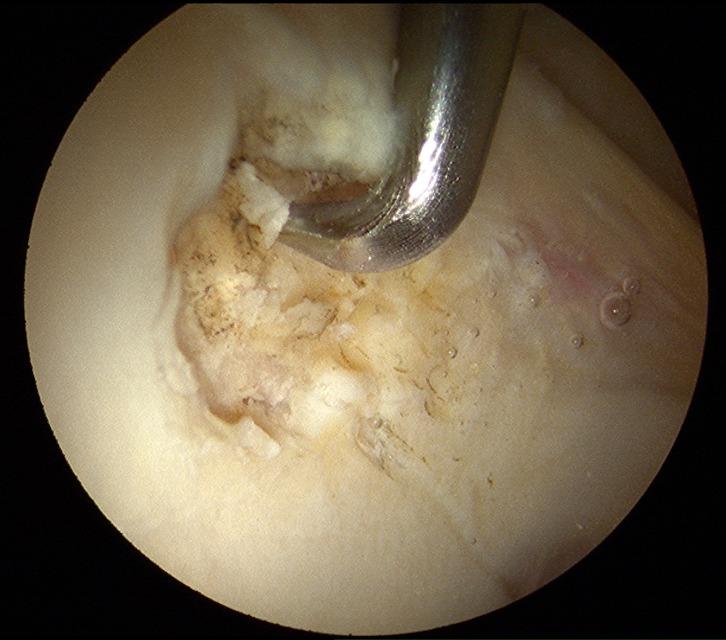

Chondrolabral complex is a weak point along an histological transition zone. Most cartilage and labral lesions in the femoroacetabular impingement syndrome are located in this area. Different classifications are used to evaluate the severity and predict the prognosis of chondrolabral complex injuries. Acetabular Labrum Articular Disruption (ALAD) and Multicenter Arthroscopy of the Hip Outcomes Research Network (MAHORN) classifications are commonly used with a prognosis and treatment implication. Treatment of chondrolabral lesions detected on magnetic resonance imaging (MRI), should only be considered when clinical symptoms are presented. A wide range of treatment options include debridement with or without microfracture, repair or regenerate therapies. The future of hip joint preservation should be directed towards to the development of the treatment of chondrolabral injuries.

髋臼唇复合体是沿着组织学过渡区的一个薄弱点。股骨髋臼撞击综合征中的大多数软骨和髋臼唇损伤都位于该区域。不同的分类方法用于评估髋臼唇复合体损伤的严重程度并预测其预后。髋臼唇关节破坏(ALAD)分类和髋关节多中心关节镜结果研究网络(MAHORN)分类是常用的,具有预后和治疗意义。只有在出现临床症状时,才应考虑对磁共振成像(MRI)检测到的髋臼唇损伤进行治疗。广泛的治疗选择包括有或无微骨折的清创术、修复或再生疗法。髋关节保留治疗的未来应朝着髋臼唇损伤治疗的发展方向前进。